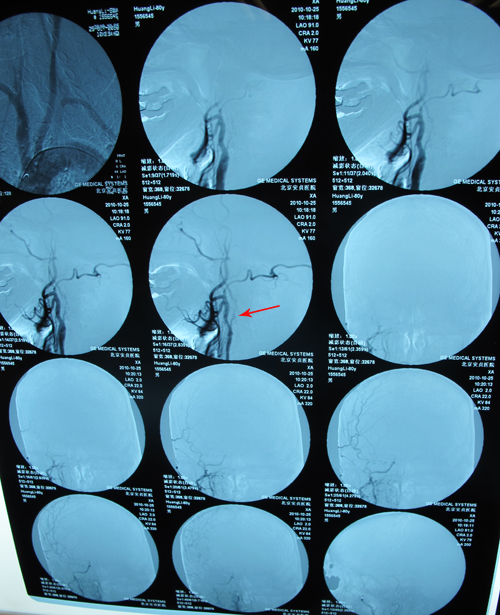

颈动脉CTA:右侧颈内动脉未见显影,左侧颈内动脉近中段管腔重度狭窄,左颈总动脉中远段、左侧颈外动脉近中段、右颈总动脉远段及分叉处管腔中度狭窄,左锁骨下动脉近段、左椎动脉中段管腔轻度狭窄,病因考虑动脉硬化。

头部血管CT造影:右侧颈内动脉颅内段次全闭塞;左侧大脑中动脉水平段以远分支管腔重度狭窄;右椎动脉远段管腔轻度狭窄,病因考虑动脉硬化;右侧大脑半球灌注异常。

脑血管成像(MRA)呈明显动脉硬化改变,以右侧颈内动脉为著。